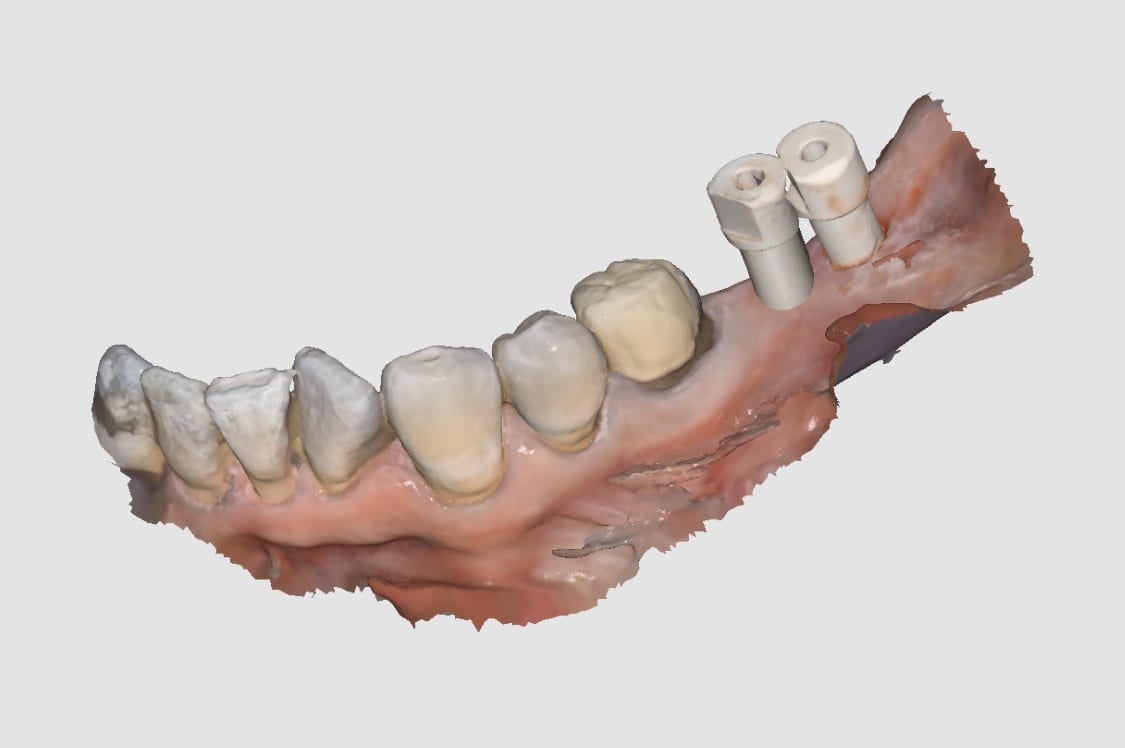

Proper Implant Placement and Digital Impressions with Scanbodies and Medit i500 Lead to Predictable Results

November 11, 2019In this video, we show a recall of an implant restored with a scanbody. When the implant was initially placed, a scanbody was seated and an X-ray was taken to […]

Implants and Digital Impressions

October 25, 2019“Yes it can I would however do separate abutments and crowns just in case you bind somewhere you can adjust crowns separate from abutments You would have struggle with analog […]